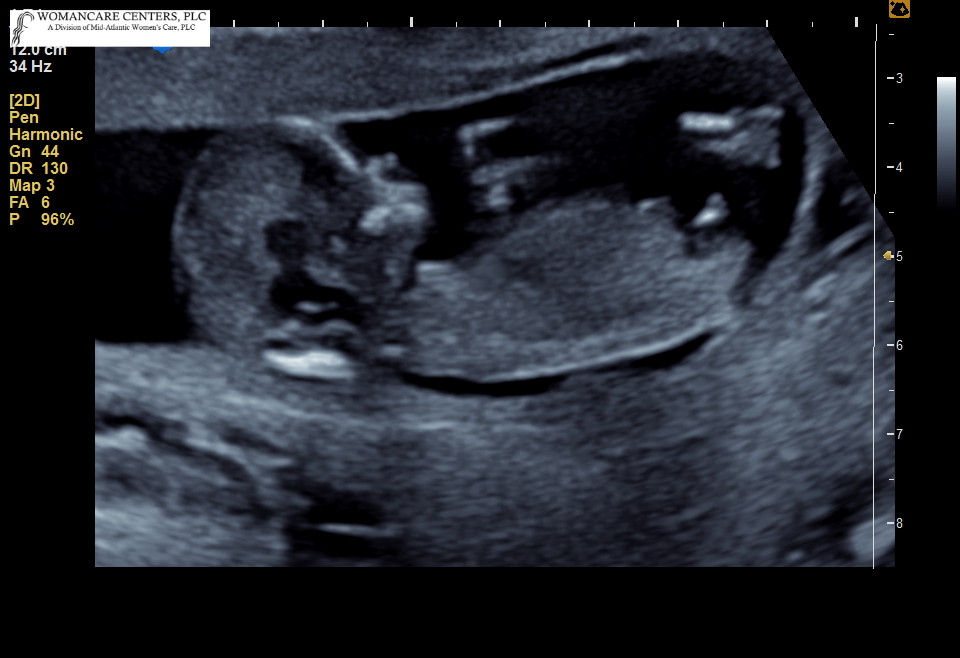

Baby measured 12 weeks and 6 days. Pretty sure I see stacking indicating boy. Any other opinions welcome! I also have a video but I'm not 100% sure it shows any nub shot. This was the only time I saw one but I'm not great at this.